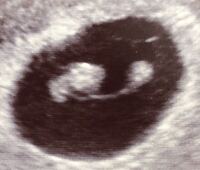

6週 心拍確認できない 小さい- 胎嚢とは?5・6・7・8週に胎嚢が小さいと言われることも? 胎嚢が小さい原因は?小さくても大丈夫? 胎嚢が小さいと流産の可能性も?障害との関係は? 心拍確認できたのに胎嚢が小さい!無事出産できる? 胎嚢が小さいと「つわりなし」というのは本当? 6週6日(6w6d・女の子・双子)|twinsmam さん(28歳) エコー写真撮影時のエピソード: 二度の初期流産を経験しています。 二度とも心拍を確認できず、流産となりました。 三度目の正直、とかなり緊張して産婦人科へ向かったのをよく覚えています。

6w入って心拍確認できませんでした。先生には、6週入ったら100%心拍確認 6w入って心拍確認できませんでした。 先生には、6週入ったら100%心拍確認できる。 次は2週間後に来て、その時どちらか確定すると言われ 不安でいっぱいです。胎芽 心拍を7週目~確認出来た時期の胎嚢の大きさを教えて下さい。私は 6週目5日ぐらいでやっと胎嚢7mmでした。胎嚢が分かったのも5週目でその時も3,9mmでした。凄く小さかったのですが、あまり成長してなくて。でも、7週目 8週目で やっと 胎芽と心拍を確無事昨日の診察で心拍を確認することができました。 6週2日ぐらいだそうです。 胎嚢141㎜ 胎芽39㎜。 このような大きさで確認できたのですが、 袋だけで診ると週数の割には小さめだと思います。 心拍確認出来れば袋のことまで気にしなくても

6週6日に心拍確認が出来ました エコー写真をもらいました こんなにハ Yahoo 知恵袋